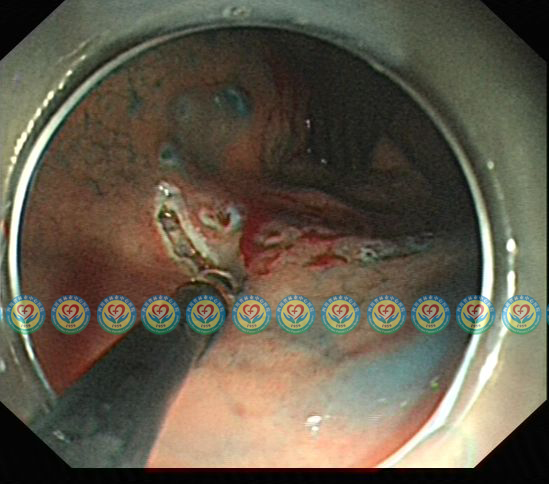

行ESD治疗,沿病灶周围标记后切开粘膜

显露粘膜下血管,逐一处理